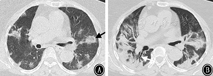

早期征象最常见的是GGO,总检出率96.9%(63/65),A、B组GGO检出率无明显差异(χ2=2.420,P=0.120)。"细网格"征共检出32例(49.2%),A、B组的检出率分别为75%(12/16)和40.8%(20/49),差异有统计学意义(χ2=4.201,P=0.04)。以反晕征为主要表现的共检出8例(12.3%),A、B组的检出率分别为18.8%(3/16),10.2%(5/49),差异无统计学意义(χ2=0.608,P=0.436),但有1例危重症患者早期表现为多发性GGO和反晕征,48 h后病灶明显进展形成肺实变(图3)。病灶内血管影增粗,共检出47例(72.3%),A、B组的检出率分别为87.5%(14/16)和67.3%(33/49),差异无统计学意义(χ2=1.160,P=0.281)。

注:黑色箭头示反晕征;白色箭头示支气管充气征

COVID-19的影像学早期征象以双肺多发GGO最为常见,这与SARS-Cov-2感染后引起肺泡壁的损伤、血管的充血和肺泡间隔的水肿有关[10]。本研究尝试对COVID-19患者的首次胸部HRCT进行分析后有如下发现。(1)病变在48 h内出现快速进展者的基线影像学特征表现为:病变多发、呈支气管血管束及外周混合分布、"细网格"影和病灶的边界模糊。这部分患者外周血淋巴细胞、CD4+T细胞减少,免疫功能低下,病灶不易局限,更易沿支气管血管束的轴向进展和蔓延[11]。而且由于淋巴细胞向靶器官迁移,导致局部的炎症反应明显使病灶的边界较为模糊。"细网格"征的检出率比较高,与SARS-Cov-2感染引起小叶间隔和小叶内间质增厚有关。(2)非快速进展者的基线影像学特征表现为:外周胸膜下外周分布的GGO、病灶边界清楚的多见。最常见分布区域的是两下肺基底段和背段,这是由于下肺和外周胸膜下区肺小叶的血流和淋巴管网分布丰富,相应小叶间质的炎性反应也更明显[12]。COVID-19病变的进展模式为以肺小叶为单位向外融合扩展,受小叶结构阻挡故而表现为具有一定的边界。推测这部分患者局部炎症反应相对较轻,病灶具有一定的自限倾向。(3)"反晕征"的检出率较低,但是曾有1例早期以多发性支气管血管束分布"反晕征"为主要表现,后期发展为肺实变的危重型病例,不排除SARS-Cov-2感染继发机化性肺炎的可能,需要引起临床足够的重视[13]。"血管影增粗"征检出率高,该征象在近期COVID-19的相关文献中也有报道[14,15],并且发现增粗的血管走行僵硬,边缘欠光整,考虑与病毒侵犯血管内皮细胞和肺泡毛细血管网,引起的血管炎有关[16]。但这两个征象与病灶的进展模式无明显相关性。